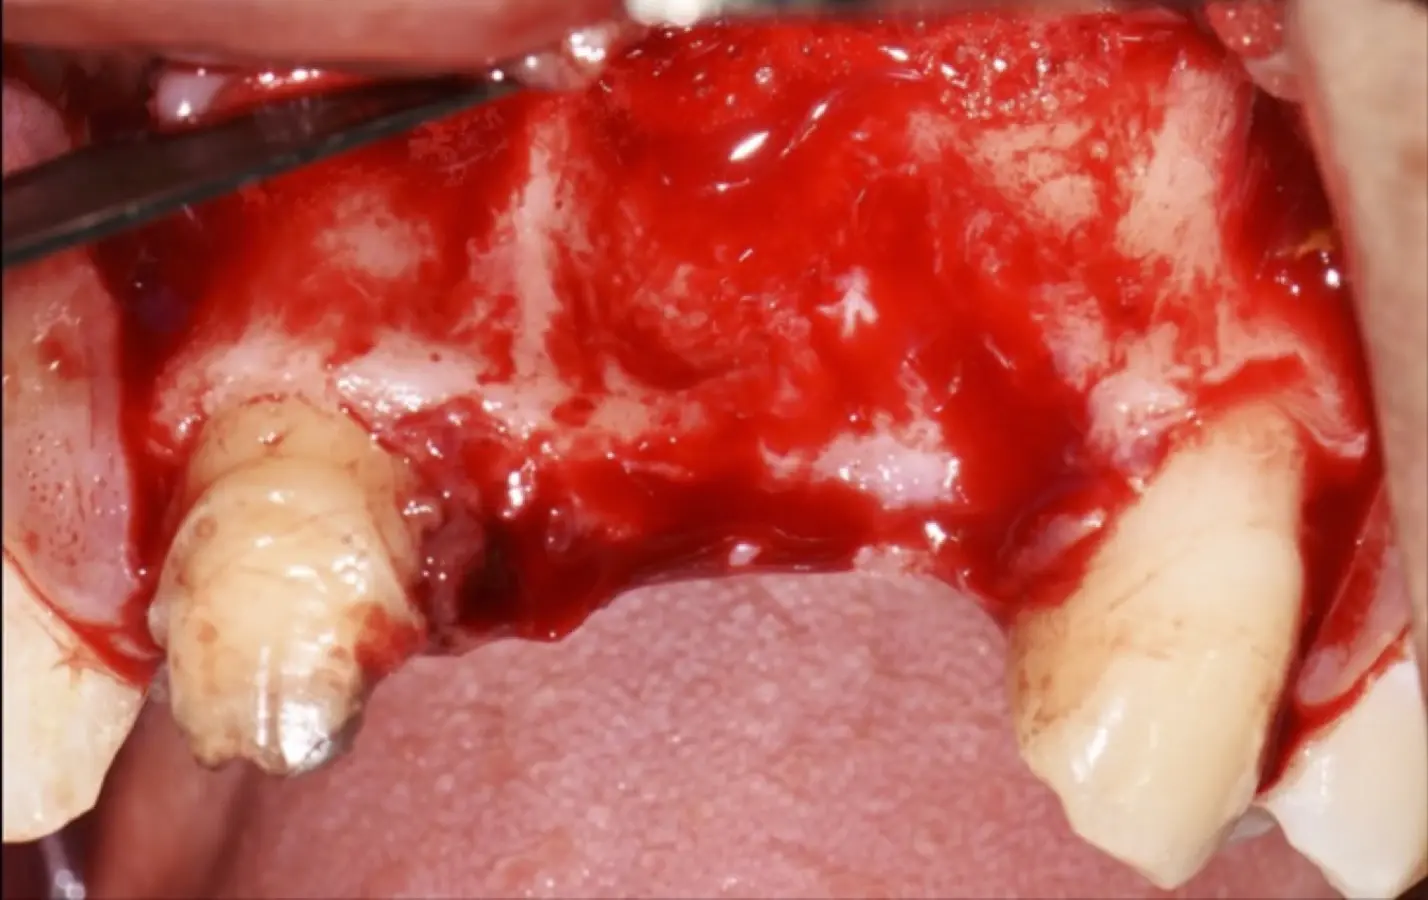

Figura 35. Decolado a espesor total sobrepasando la línea mucogingival (a, b).

Figura 36. Defecto óseo y severa reabsorción ósea horizontal: vista clínica (a) y corte tomográfico (b).